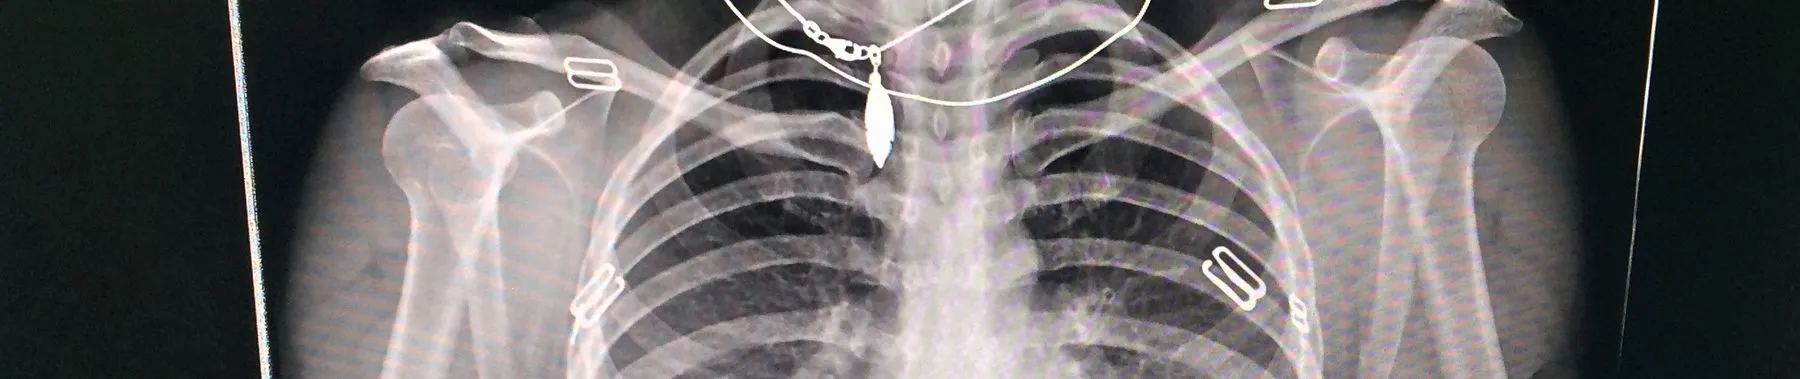

AI-Based Medical Image Classification: Deep learning is now a standard tool for assisting radiologists. Building a model to detect pneumonia from X-rays or lesions from MRIs teaches the importance of model sensitivity, specificity, and the ethical implications of diagnostic AI.

Semantic Segmentation with U-Net: Unlike classification, segmentation requires pixel-level precision. Implementing a U-Net architecture to isolate tumors or organs in medical scans demonstrates a developer’s ability to handle high-stakes, grayscale data with complex boundaries.